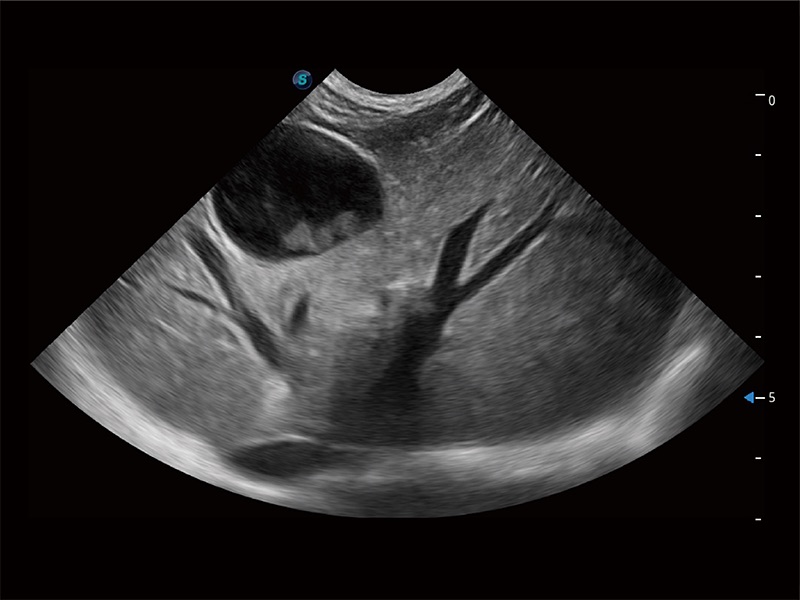

高性能和先进的临床应用工具可以为动物医生提供临床信心。ProPet 80 搭载了先进的腹部和浅表应用工具,帮助医生在日常临床实践中发挥前所未有的作用。

为精细结构及组织边缘提供高清晰度的图像和更大的成像视野。帮助减轻医生的用眼疲劳,快速精准获得测量的数据。